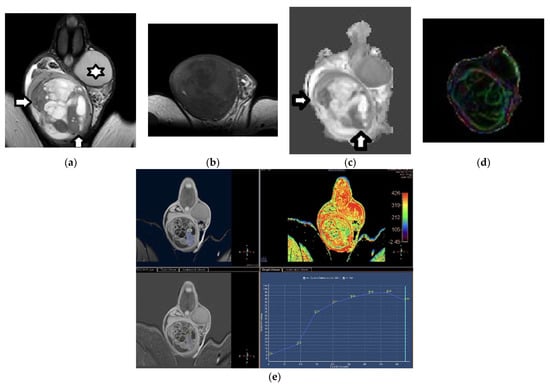

2.3. Dynamic Contrast-Enhanced MRI

- Tsili, A.C.; Argyropoulou, M.I.; Astrakas, L.G.; Ntoulia, E.A.; Giannakis, D.; Sofikitis, N.; Tsampoulas, K. Dynamic contrast-enhanced subtraction MRI for characterizing intratesticular mass lesions. AJR Am. J. Roentgenol. 2013, 200, 578–585. [Google Scholar] [CrossRef]

- El Sanharawi, I.E.; Correas, J.M.; Glas, L.; Ferlicot, S.; Izard, V.; Ducot, B.; Bellin, M.F.; Benoît, G.; Rocher, L. Non-palpable incidentally found testicular tumors: Differentiation between benign, malignant, and burned-out tumors using dynamic contrast-enhanced MRI. Eur. J. Radiol. 2016, 85, 2072–2082. [Google Scholar] [CrossRef]

- Tsili, A.C.; Sylakos, A.; Ntorkou, A.; Stavrou, S.; Astrakas, L.G.; Sofikitis, N.; Argyropoulou, M.I. Apparent diffusion coefficient values and dynamic contrast enhancement patterns in differentiating seminomas from nonseminomatous testicular neoplasms. Eur. J. Radiol. 2015, 84, 1219–1226. [Google Scholar] [CrossRef]

| Manganaro et al. (2018) [90] | To explore the role of DCE-MRI using semi-quantitative and quantitative parameters and DWI in differentiating benign from malignant small, non-palpable, solid testicular tumors | 1.5 T | 0, 500, 1000 | Higher percentages of peak enhancement, wash-in-rate, volume transfer constant, rate constant, and initial area under the curve, and shorter time to peak, in benign lesions compared to malignancies Higher percentages of peak enhancement, wash-in-rate, volume transfer constant, rate constant, and initial area under the curve, and shorter time to peak, in LCTs compared to seminomas Best diagnostic cutoff for identification of seminomas: volume transfer constant, ≤0.135 min−1; rate constant, ≤0.45 min−1; initial area under the curve, ≤ 10.96; wash-in-rate, ≤1.11; percentage of peak enhancement, ≤96.72; time to peak, >99 s All tumors had similar ADC | Majority of lesions: LCTs and seminomas; no other histological types Palpable masses > 1.5 cm excluded Small tumor size may influence MRI measurements 50% of cases referred for infertility |